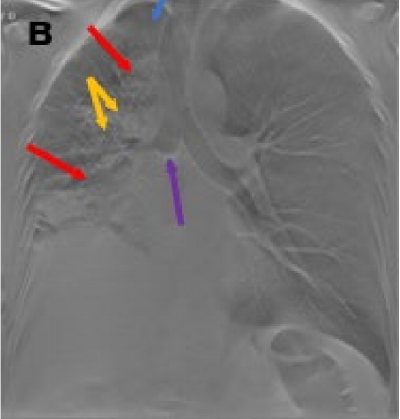

На рисунке состояние после лапароскопии, торакотомии, расширенной субтотальной резекции пищевода с одномоментной пластикой широким желудочным стеблем и анастомозом в плевральной полости. На рентгенограмме грудной полости в нижней доле правого лёгкого определяется фокус неоднородного уплотнения лёгочной паренхимы (красные стрелки) – воспалительные изменения? желудочный стебель? В левой плевральной полости гидроторакс (жёлтая стрелка). При ТС – в правом гемитораксе определяется расширенный желудочный стебель – гастростаз (зелёные стрелки) – с неоднородным содержимым, наличием в нем газа (синие стрелки). Гидроторакс слева (жёлтые стрелки).